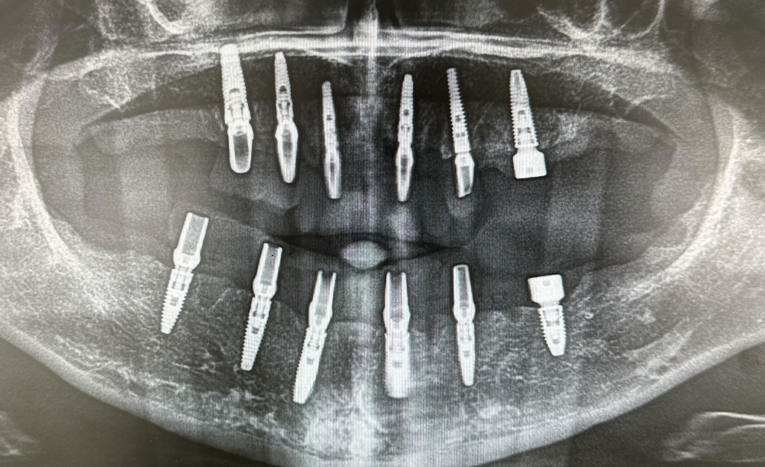

Foto: Dental Centar Jelić

Dentalni implantati ugrađuju se u čeljust i njihovo učvršćivanje traje 3 do 4 mjeseca – kontrolira se rendgen slikom.

Kontrola rendgen slikom. Foto: Dental Centar Jelić